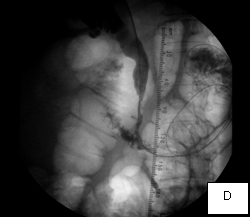

The second case was a woman with obstructive jaundice from cancer of the head of the pancreas, which produced a tapering narrowing of her common bile duct. In her, I crossed the diseased duct by cannulating a right intrahepatic duct from a right percutaneous puncture. Once I secured the access with a sheath, I was able to cross the obstruction with a stiff glidewire (image D) over which I deployed a Wallstent (image F).